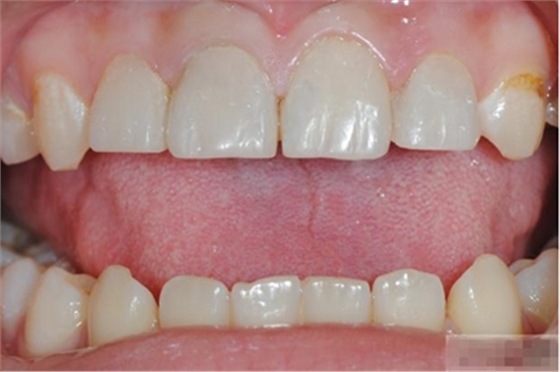

【主訴】上前牙充填物脫落兩個(gè)月

【病史】上前牙一年前行根管治療,充填物部分脫落,自覺(jué)影響美觀,從不敢笑,要求先行樹(shù)脂修復(fù)。(年齡:14歲)

【檢查】12,11,21,22,均行玻璃離子充填,各牙不同程度部分充填物脫落,探(—),叩(—),冷刺激無(wú)反應(yīng),無(wú)松動(dòng),牙齦顏色粉紅,質(zhì)地堅(jiān)實(shí)而有彈性,點(diǎn)彩正常,牙結(jié)石(—);牙髓活力測(cè)試無(wú)反應(yīng)。

【診斷】12,11,21,22牙體缺損